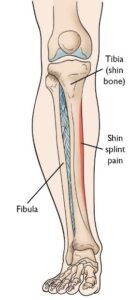

Το σύνδρομο έσω κνημιαίας κόπωσης είναι ένα κοινό πρόβλημα που σχετίζεται με την άσκηση. Ο όρος αναφέρεται στον πόνο κατά μήκος της εσωτερικής άκρης της κνήμης.

Σε γενικές γραμμές, το σύνδρομο αναπτύσσεται όταν οι μύες και το περιόστεο καταπονούνται υπερβολικά από επαναλαμβανόμενη δραστηριότητα.

Το πιο συνηθισμένο σύμπτωμα είναι ο πόνος στην έσω επιφάνεια της κνήμης. Μπορεί επίσης να εμφανιστεί και ήπιο οίδημα στην περιοχή.